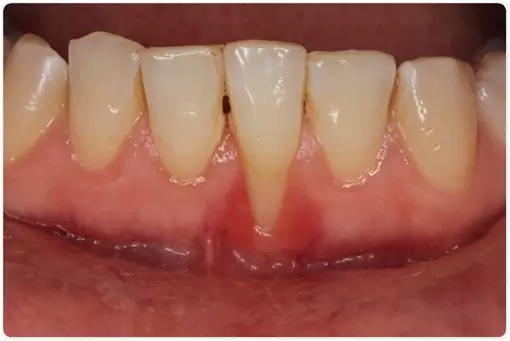

The longer plaque and tartar are on teeth, the more harmful they become. The bacteria cause inflammation of the gums that is called “gingivitis.” In gingivitis, the gums become red, swollen and can bleed easily. Gingivitis is a mild form of gum disease that can usually be reversed with daily brushing and flossing, and regular cleaning by a dentist or dental hygienist.